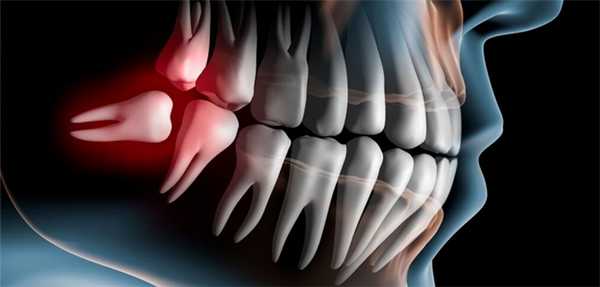

Дистопированный зуб - зуб, занимающий неправильное положение в зубном ряду или смещенный за пределы альвеолярного отростка челюсти. К вариантам дистопии относят вестибулярное, оральное, мезиальное, дистальное расположение зуба, инфраположение, супраположение, тортопозицию и транспозицию. Дистопированные зубы представляют косметический и функциональный недостаток; могут способствовать формированию неправильного прикуса, хронической травматизации слизистой оболочки полости рта, развитию перикоронарита, сочетаться с ретенцией. Дистопированные зубы выявляются в процессе стоматологического осмотра, изучения ортопантомограмм, моделей челюстей и телерентгенограмм. В зависимости от своего расположения дистопированные зубы могут подлежать ортодонтическому лечению или удалению.

Дистопированный зуб (дистопия) - аномалия зуба, характеризующаяся его неправильным положением в зубной дуге или за ее пределами и затрудняющая прорезывание других зубов. В стоматологии под правильным положением зубов понимают строго определенную позицию, соответствующую каждому зубу в зубном ряду, а также его взаимоотношения с соседними зубами и зубами-антагонистами на противоположной челюсти. Зубы, выросшие со смещением или наклоном, а также прорезавшиеся вне зубной дуги, считаются дистопированными. Чаще всего дистопированными бывают нижние третьи моляры («зубы мудрости»), верхние и нижние резцы, верхние клыки; реже - верхние и нижние премоляры и верхние третьи моляры. Дистопия зубов часто сочетается с ретенцией, дистальным, мезиальным, открытым прикусом, скученностью зубов и пр.

Частным случаем дистопированного зуба мудрости является непрорезавшаяся, но полностью сформировавшаяся восьмерка, оказавшаяся повернутой параллельно десне. В этом случае зуб есть, хоть его и не видно, и он находится в некорректном положении, поэтому можно говорить о дистопии.

Два примера дистопии зубов